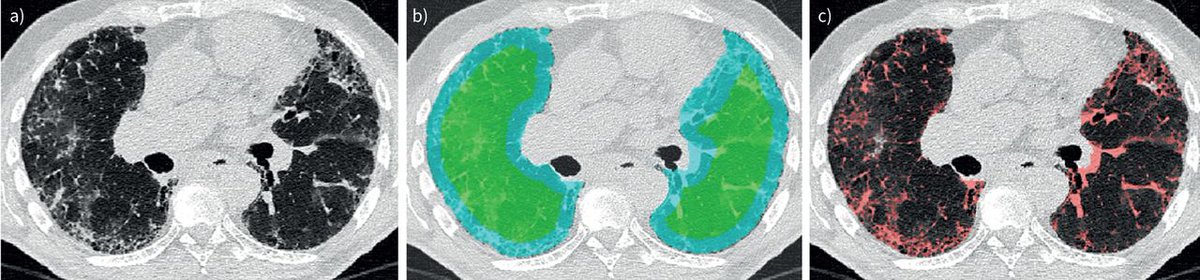

Excited for another busy #ATS2025, with Peter George and Prof Anand Devaraj presenting the latest evidence for our FDA-cleared e-Lung technology, which has been robustly validated in the #INBUILD study to identify progressive pulmonary fibrosis accurately and sensitively.

✅ e-Lung is robustly validated in the #INBUILD study to identify progressive pulmonary fibrosis accurately and sensitively ✅ e-Lung helps to identify patients at risk of progressive pulmonary fibrosis We hope to see you in San Francisco! 🌉 Peter George American Thoracic Society (ATS)